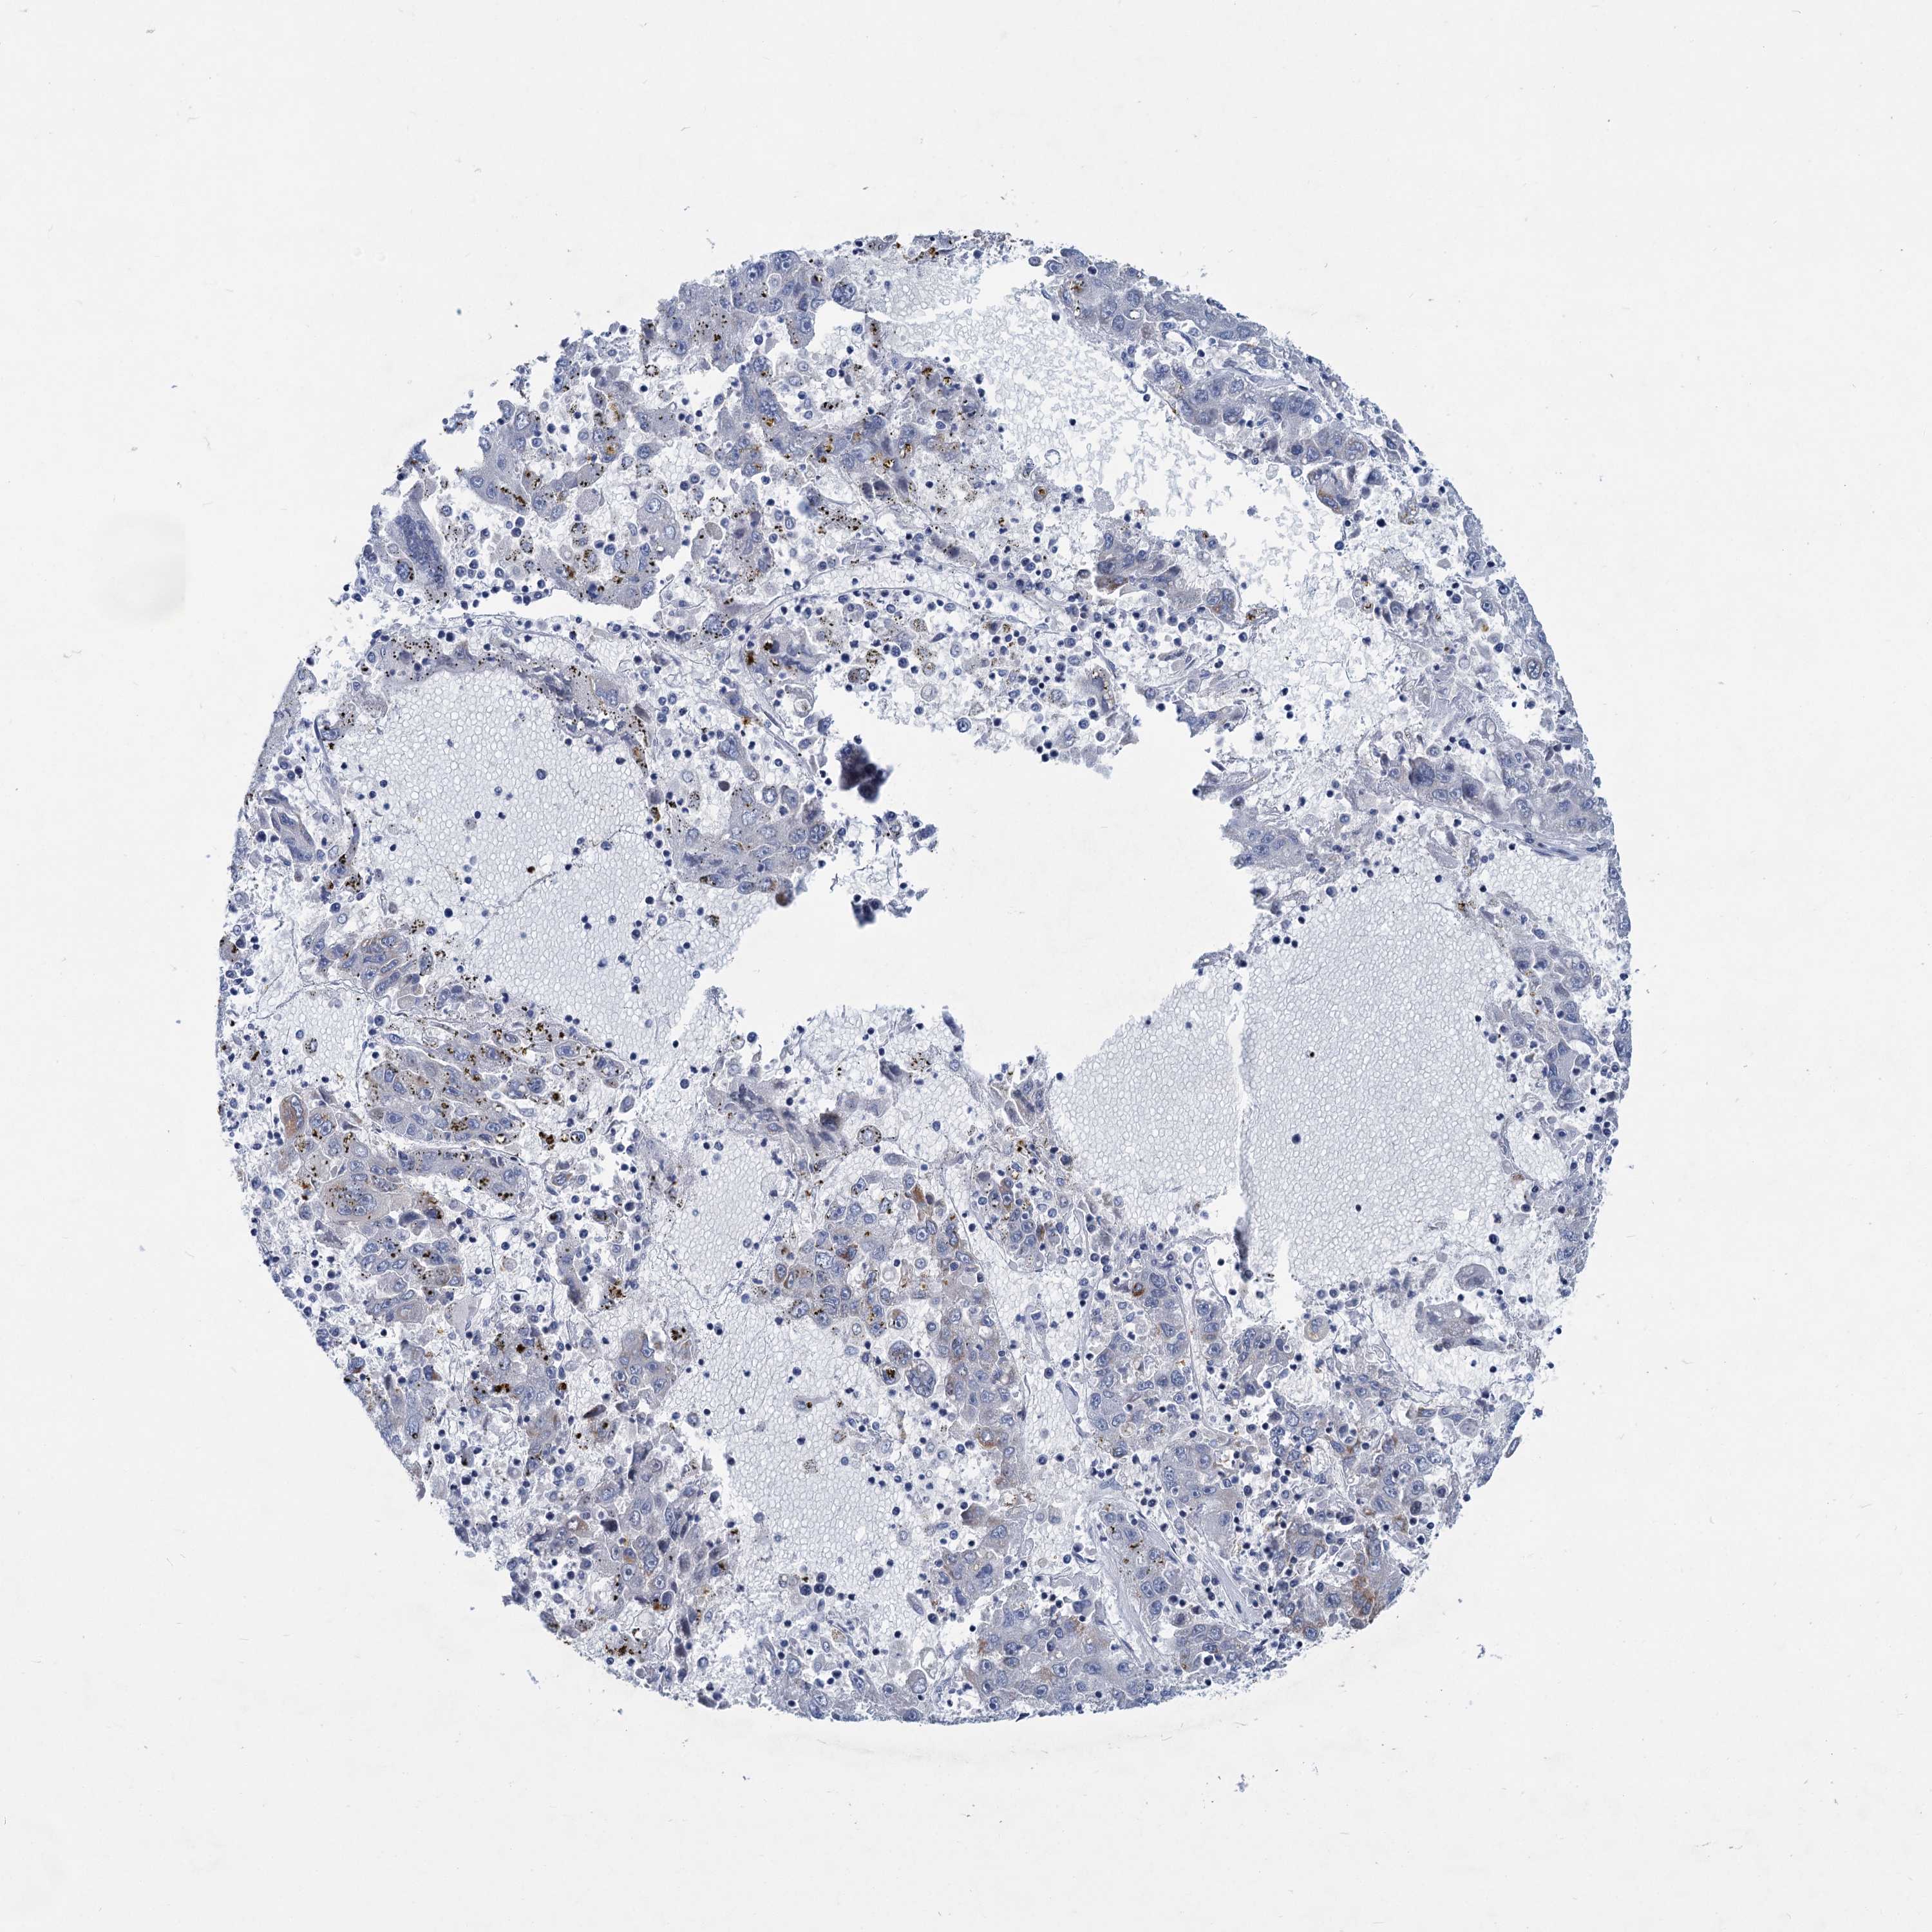

LIVER CANCER - Protein expressioni

A mouse-over function shows sample information and annotation data. Click on an image to view it in a full screen mode. Samples can be filtered based on level of antibody staining by selecting one or several of the following categories: high, medium, low and not detected. The assay and annotation is described here.

Antibody stainingi

Antibody staining in the annotated cell types in the current human tissue is reported as not detected, low, medium, or high, based on conventional immunohistochemistry profiling in selected tissues. This score is based on the combination of the staining intensity and fraction of stained cells.

Each image is clickable and will lead to virtual microscopy that enables deeper exploration of all samples and also displays staining intensity scores, fraction scores and subcellular localization as well as patient and tissue information for each sample.

Antibody HPA036633

Antibody HPA058130

Staining

High

Medium

Low

Not detected

Intensity

Strong

Moderate

Weak

Negative

Quantity

>75%

75%-25%

<25%

None

Location

Nuclear

Cytoplasmic/membranous

Cytoplasmic/membranous,nuclear

Cholangiocarcinoma

Carcinoma, Hepatocellular, NOS